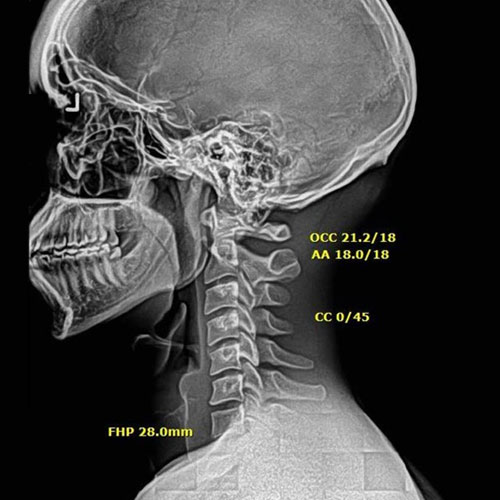

After Corrective Chiropractic Care: Following a customized course of corrective chiropractic treatment, repeat X-rays demonstrated measurable improvement in cervical alignment. More importantly, those structural changes translated into real-life results — reduced pain, improved function, and a return to daily activities with confidence.

This is the difference between symptom-based care and corrective care.